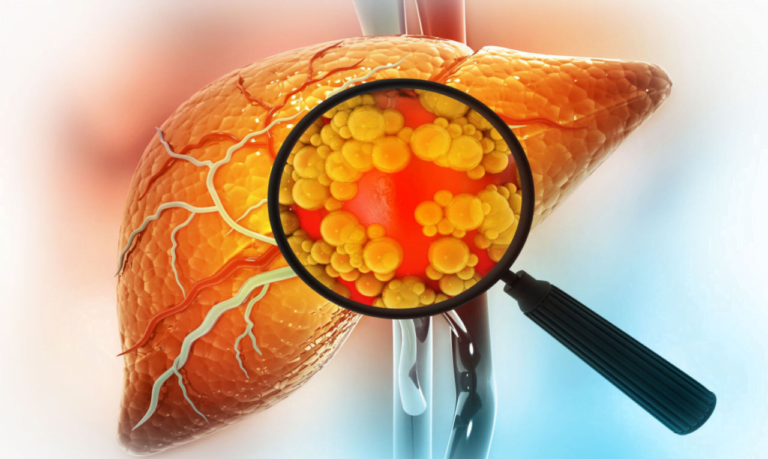

Suco Detox: Um Aliado Poderoso para o Bem-Estar do Fígado

O fígado é um dos órgãos mais importantes do nosso corpo, desempenhando funções cruciais para a nossa saúde. Infelizmente, a má alimentação e o consumo excessivo de bebida alcoólica foram levados cada vez mais pessoas a serem diagnosticados com a…